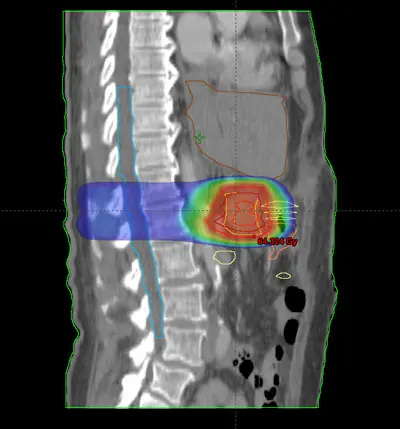

Radioterapia